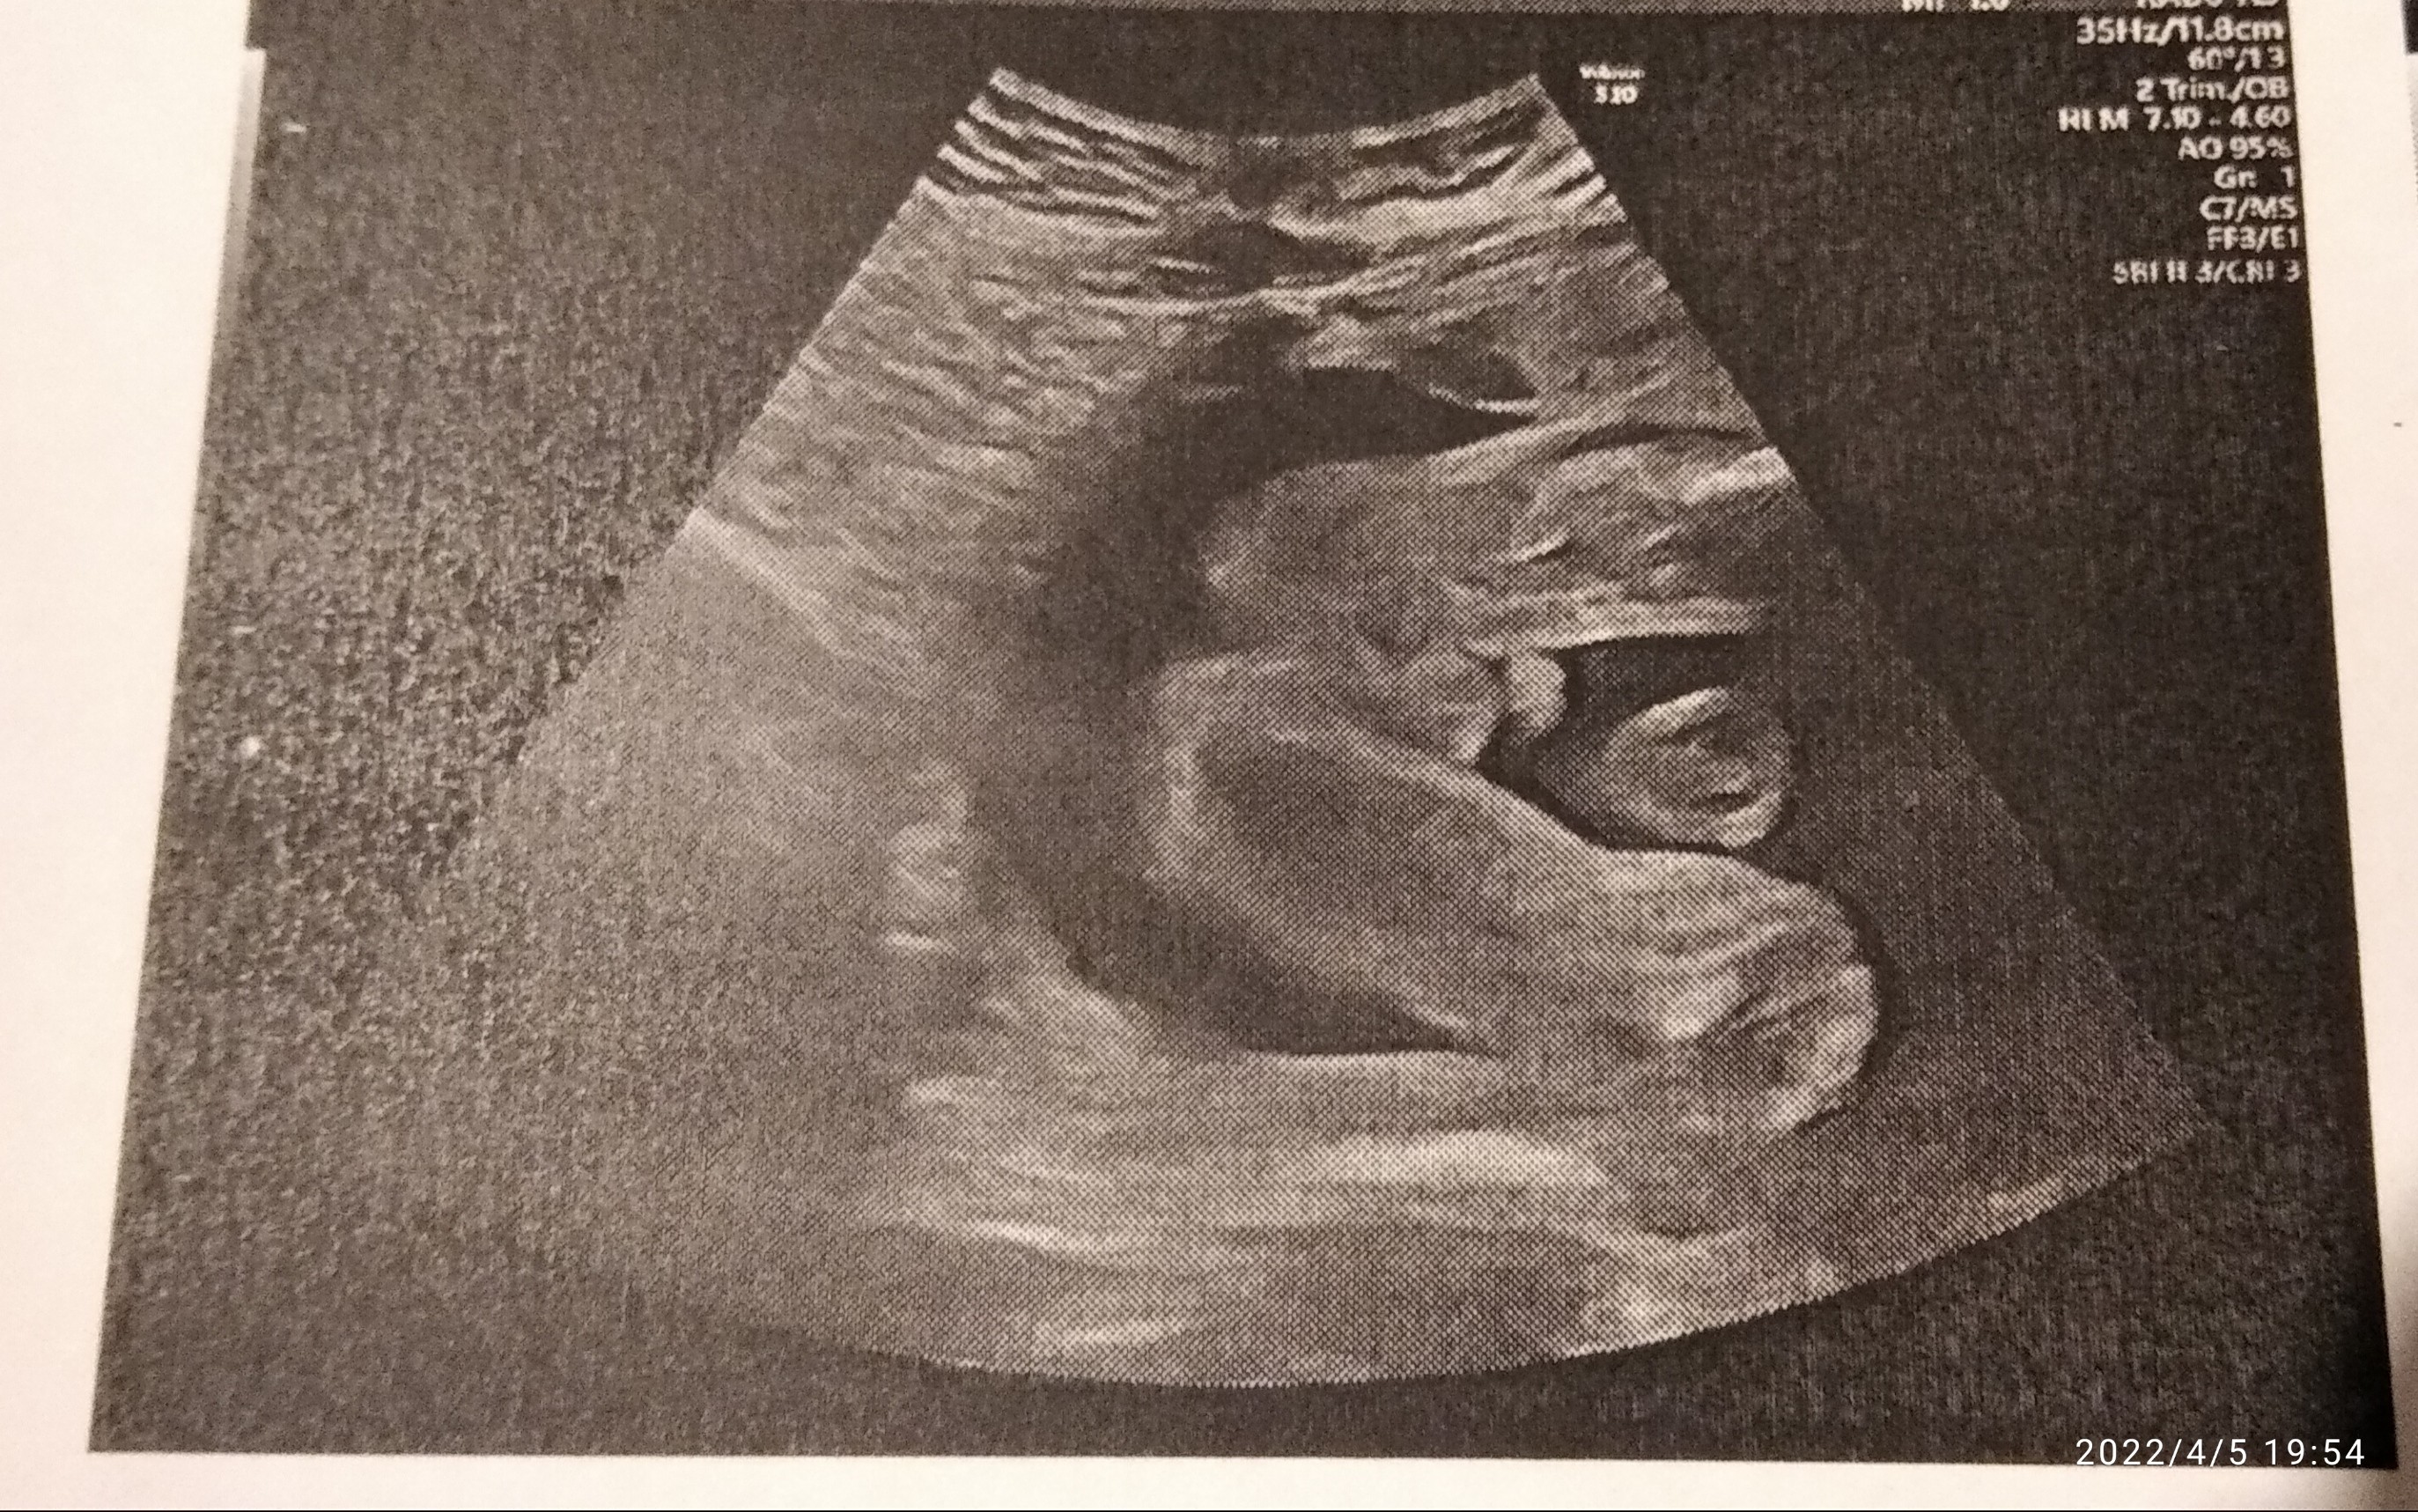

SuperWitam, u mnie się potwierdziło, będzie chłopak![]()

ale sie wystawiłWitam, u mnie się potwierdziło, będzie chłopak![]()